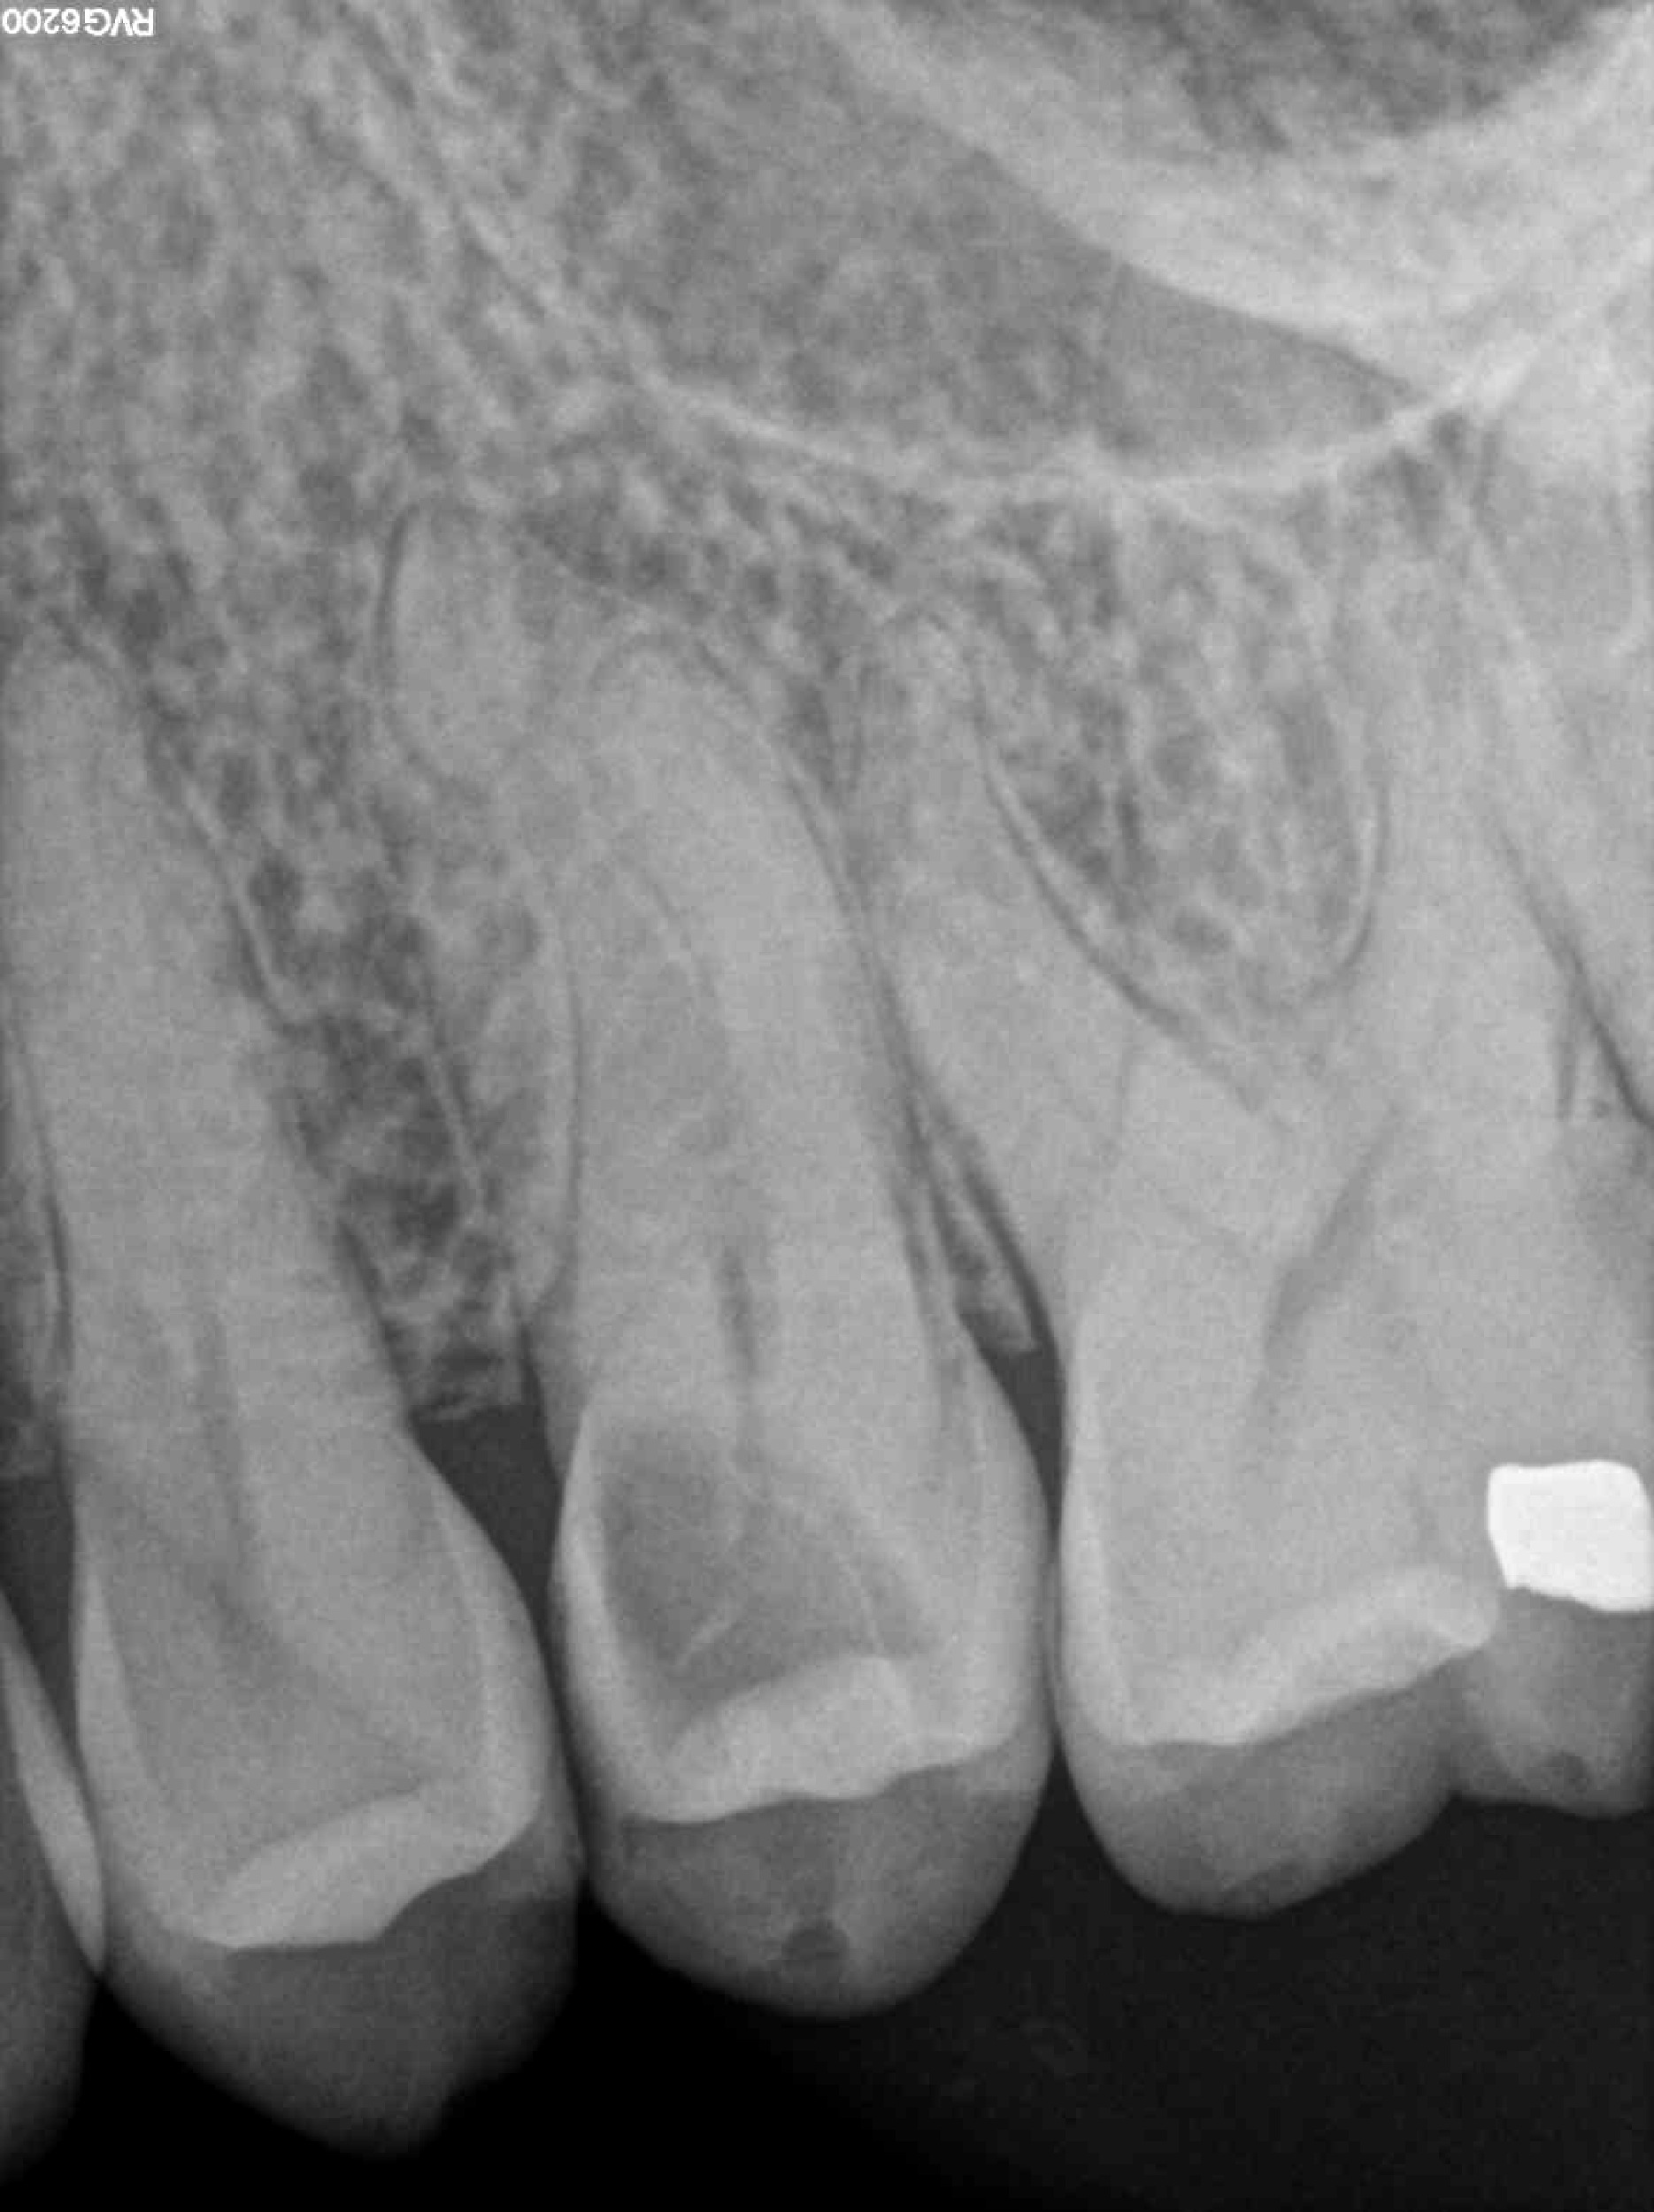

* Haz click sobre las radiografías para verlas a mayor tamaño

Haz click sobre las radiografías para verlas a mayor tamaño